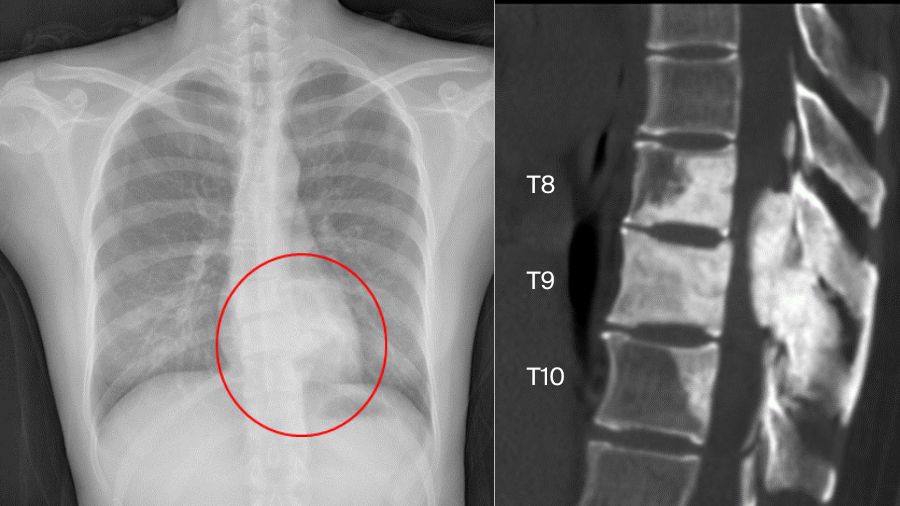

But sometimes things are more complicated. Another case involved a 33-year-old female. The chest X-ray examination found an osteogenic spinal lesion. The CT scan showed osteolytic lesions of T9 left vertebral body, facet joints and rib, with extensive reactive bone formation.

There was obvious spinal cord compression, and the PET/CT revealed extensive uptake.

We did a CT-guided biopsy. Although we consulted the result in three hospitals, the pathologists failed to give us a definite diagnosis, whether it was osteoblastoma or a low-grade osteosarcoma.

So, we treated it as if it was malignant. We did an anterior-posterior approach sagittal en bloc resection of the T8 to T10. In the anterior approach, we dissected the tumor. In posterior approach, we transected the body with an ultrasonic cutter. We resected three segments en bloc. The margin was sufficient, not only pathologically, but also by CT scan.

The postoperative pathological diagnosis is still unclear. The pathologists gave us four diagnoses: osteoblastoma, epithelioid osteoblastoma, low-grade osteosarcoma, or even osteomyelitis.

Nevertheless, the patient was doing well in the 2-year follow-up. There is no recurrence.